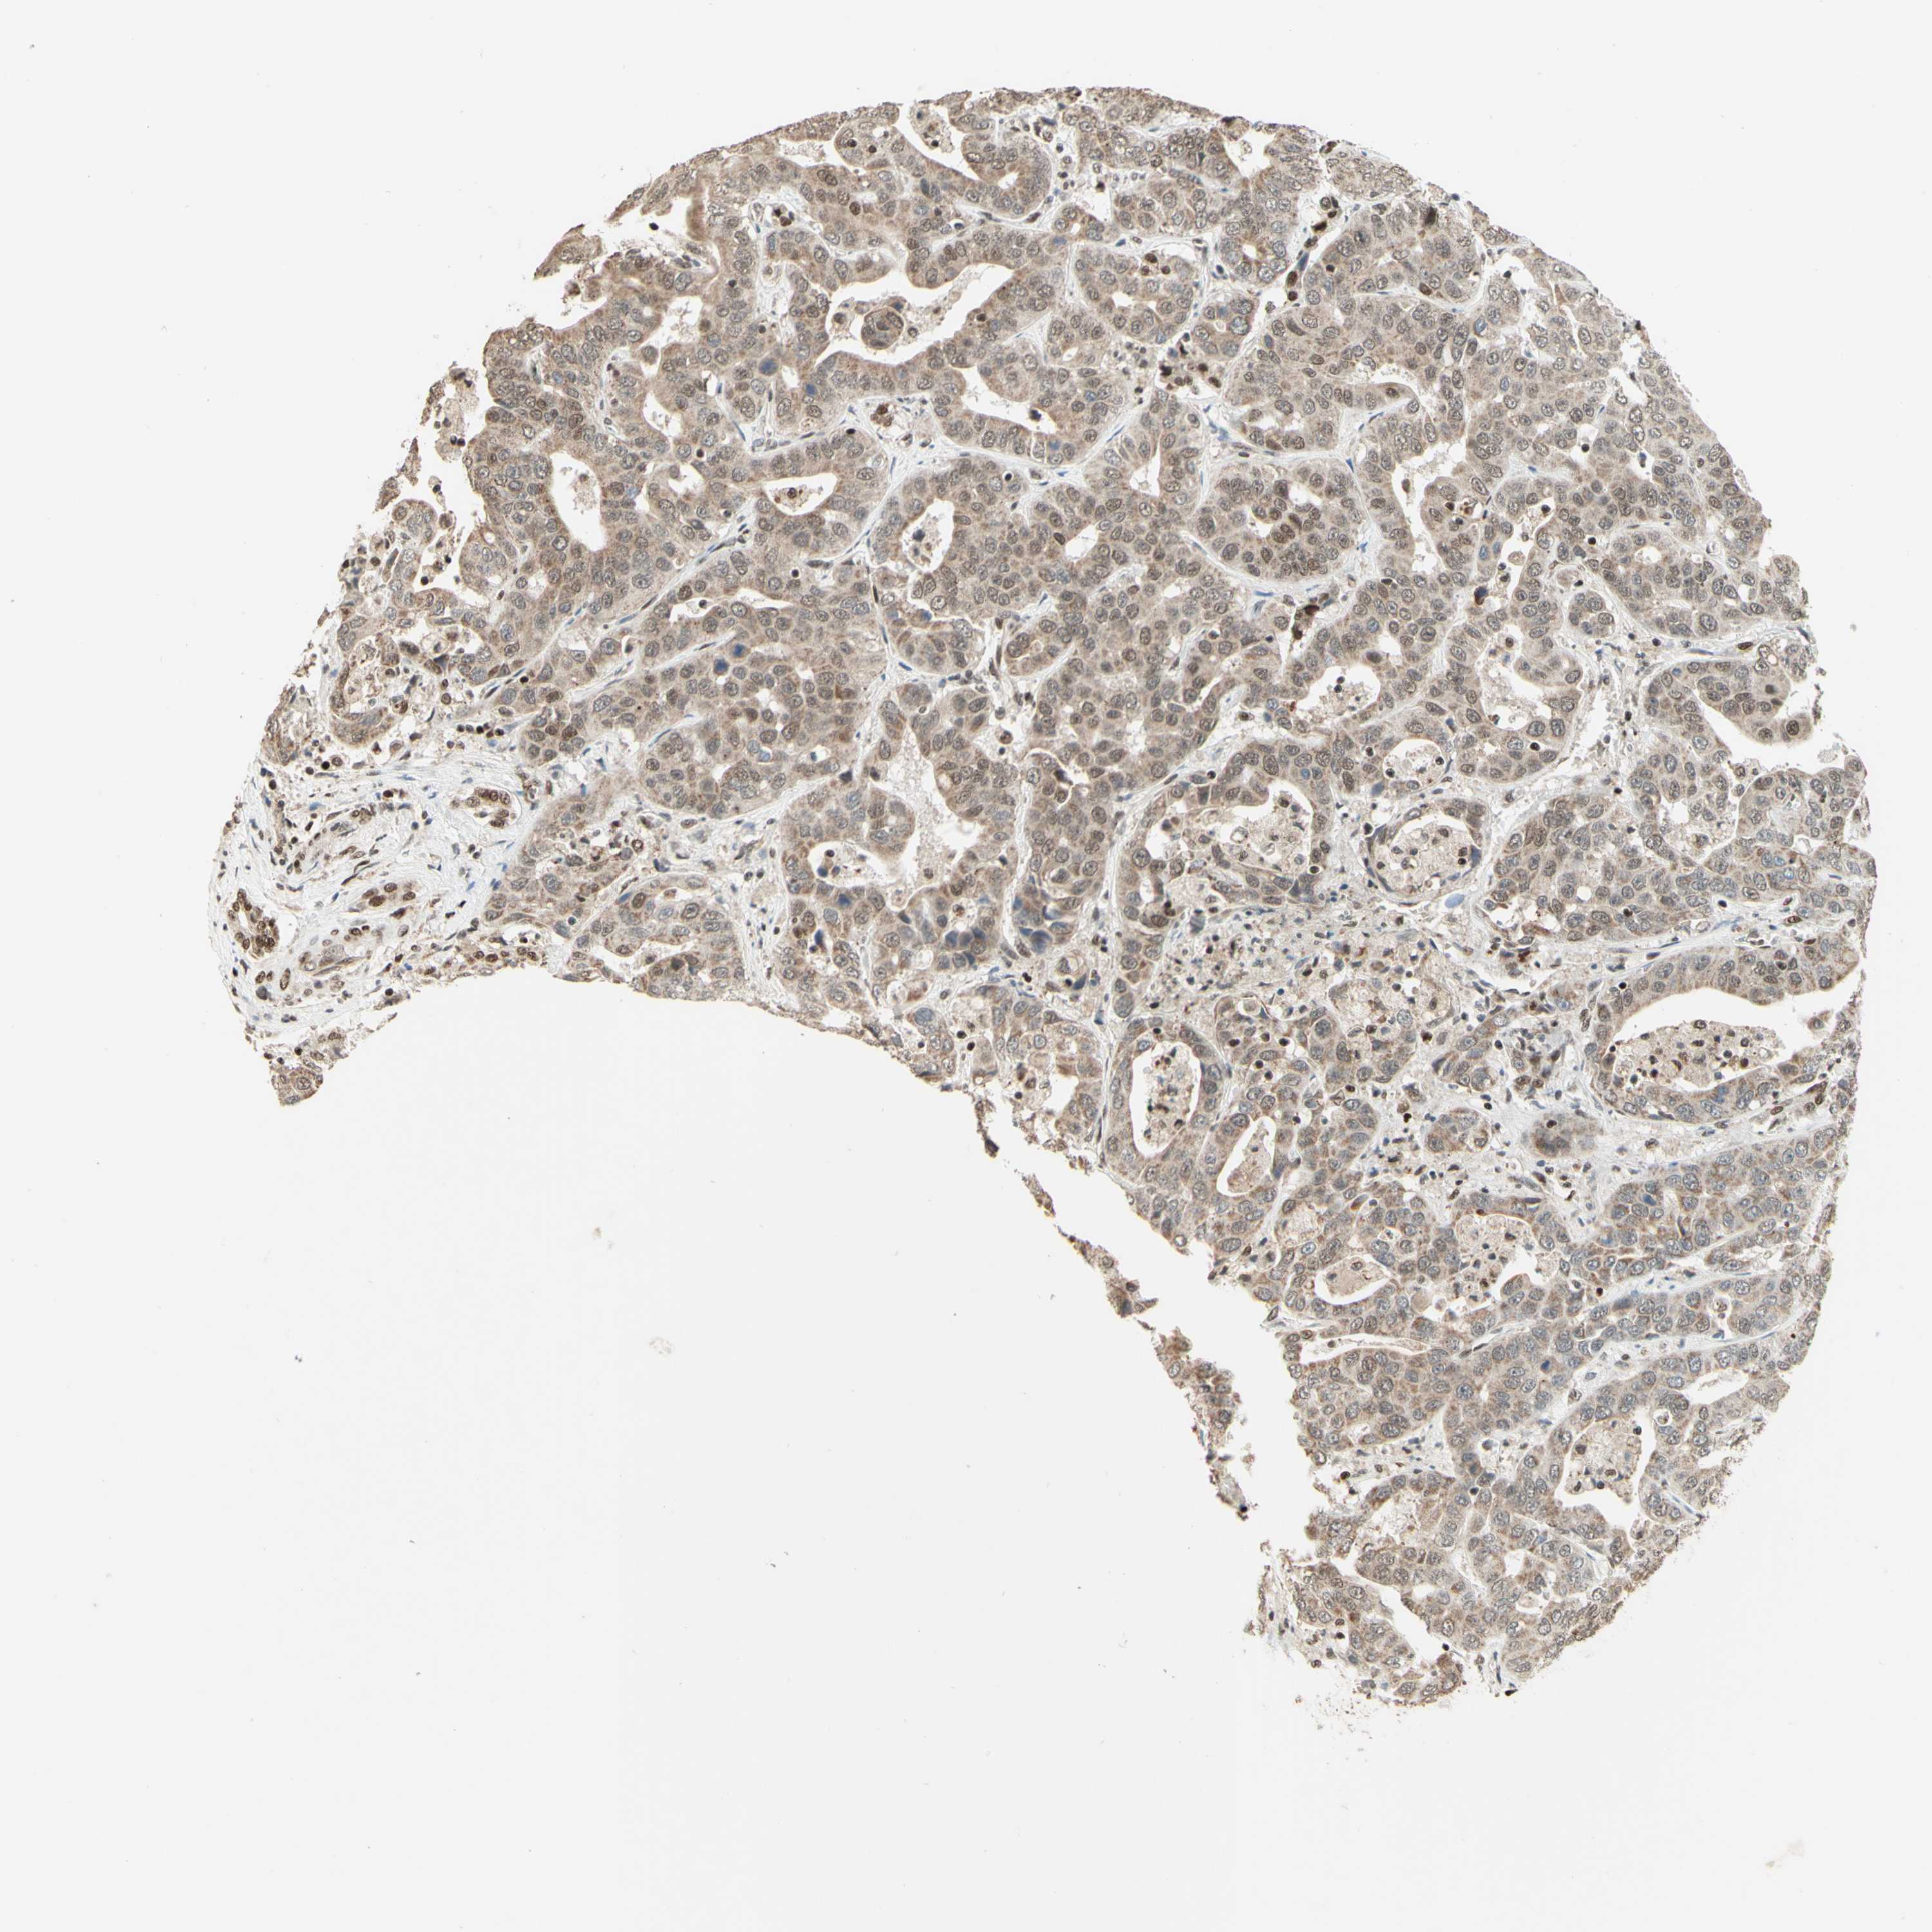

LIVER CANCER - Protein expressioni

A mouse-over function shows sample information and annotation data. Click on an image to view it in a full screen mode. Samples can be filtered based on level of antibody staining by selecting one or several of the following categories: high, medium, low and not detected. The assay and annotation is described here.

Note that samples used for immunohistochemistry by the Human Protein Atlas do not correspond to samples in the TCGA dataset.

Antibody stainingi

Antibody staining in the annotated cell types in the current human tissue is reported as not detected, low, medium, or high, based on conventional immunohistochemistry profiling in selected tissues. This score is based on the combination of the staining intensity and fraction of stained cells.

Each image is clickable and will lead to virtual microscopy that enables deeper exploration of all samples and also displays staining intensity scores, fraction scores and subcellular localization as well as patient and tissue information for each sample.

Antibody HPA004248

Antibody CAB010435

Staining

High

Medium

Low

Not detected

Intensity

Strong

Moderate

Weak

Negative

Quantity

>75%

75%-25%

<25%

None

Location

Nuclear

Cytoplasmic/membranous

Cytoplasmic/membranous,nuclear

Cholangiocarcinoma

Carcinoma, Hepatocellular, NOS